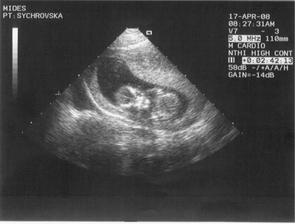

A pokračujeme dál : 17.4.2008 jsme navštívili nemocnici v Ústí nad Labem kvůli srdíčku miminka,zda nemá po manželovi vrozenou vadu,prozatím je vše v pořádku,ale 19.6.2008 jedeme na kontrolu.

Jinak od 24.4.08 chodime každý čtvrtek do bazenu na plavání pro těhotné,krásně se u toho člověk protáhne.Kvůli problemům s ledvinami to máme bohužel už zakázané☹ 20.5.08 nam vzali krev na vrozené vady-včera jsme se dozvěděli že jsme zdraví,jupíííí 🙂 5.6.2008 jdeme do poradny,kde nám pan doktor už možná bude moci říct jestli jsme chlapeček nebo holčička,tak uvidíme.Máme trochu problémy s ledvinami,ale miminku to neublíží a je v pořádku.Akorát já trpím bolestma☹ Ale kvůli prckovi se to vydrží🙂 Tak po včerejší kontrole toho víme zase o trochu víc - nejspíš čekáme holčičku,ale uvidí se ještě na dalších kontrolách.Další velký ultrazvuk máme za sebou,vše je OK.Akorát tentokrát nám řekli že to bude chlapeček,takže jsme na tom tak jako na začátku🙂 Jinak 19.6.08 proběhla kontrola v Ústí kvůli srdíčku - je v pořádku a máme malého kulíška i na videu🙂Teď nás čeká poradna 3.7.08.Prcek už 2 týdny hezky kope,je to neskutečně příjemný pocit😀Kontrola v poradne probehla v poradku,mimisek je zdravy,kope a ma se cile k svetu.8.7.08 jdeme na vyšetření jestli nemáme cukrovku-nic příjemného ale dá se to vydržet🙂